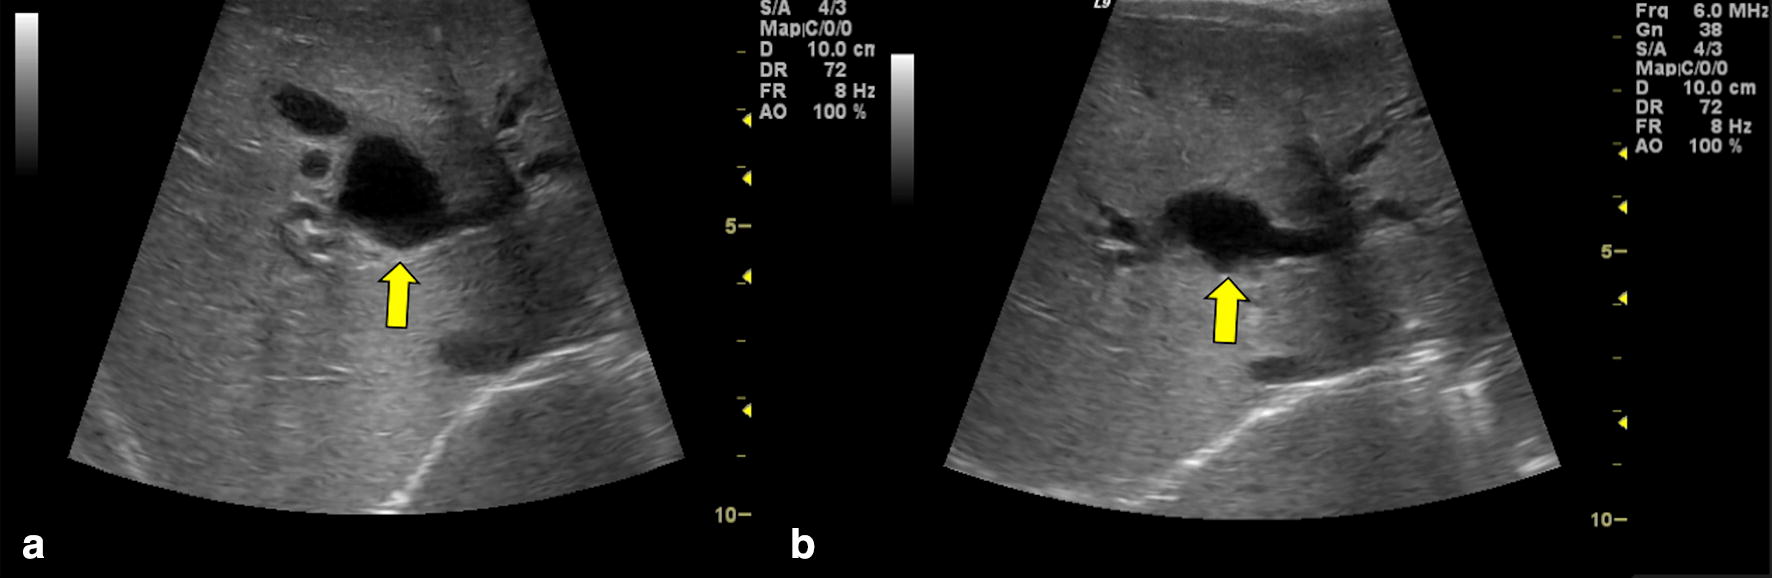

Escherichia coli sepsis with chronic cholestasis. Inspissated bile Cholestasis Ultrasound Findings Bile is the digestive fluid produced. the term cholestasis is commonly referred to an impairment of. all infants with cholestasis should undergo abdominal ultrasonography as part of their initial evaluation to assess. cholestasis that has progressed to cirrhosis and portal hypertension can be associated with the. cholestasis represents an impaired secretion of bilirubin by hepatocytes, manifesting. Cholestasis Ultrasound Findings.

Persistent Neonatal Cholestasis in a Preterm Infant Consultant360 Cholestasis Ultrasound Findings cholestasis represents an impaired secretion of bilirubin by hepatocytes, manifesting with high blood. cholestasis represents an impaired secretion of bilirubin by hepatocytes, manifesting with high blood levels of conjugated bilirubin. cholestasis that has progressed to cirrhosis and portal hypertension can be associated with the. all infants with cholestasis should undergo abdominal ultrasonography as part of their. Cholestasis Ultrasound Findings.